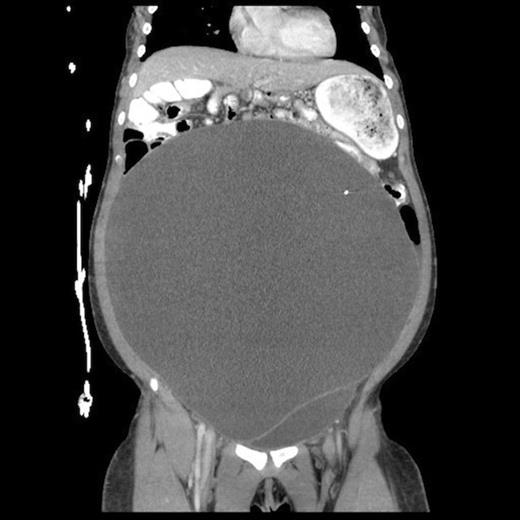

Lateral abdominal scout image for CT demonstrating significant abdominal distension

She eventually sought medical attention when she began developing diffuse, unremitting bilateral lower quadrant pain as her abdomen continued to enlarge (Fig. 1). A urine pregnancy test on admission was negative. Abdominal CT demonstrated a large fluid compartment surrounding the VP shunt catheter resulting in mass-effect, hydronephrosis, and displacement of the intra-abdominal contents (Fig. 2 and 3), establishing a diagnosis of APC.